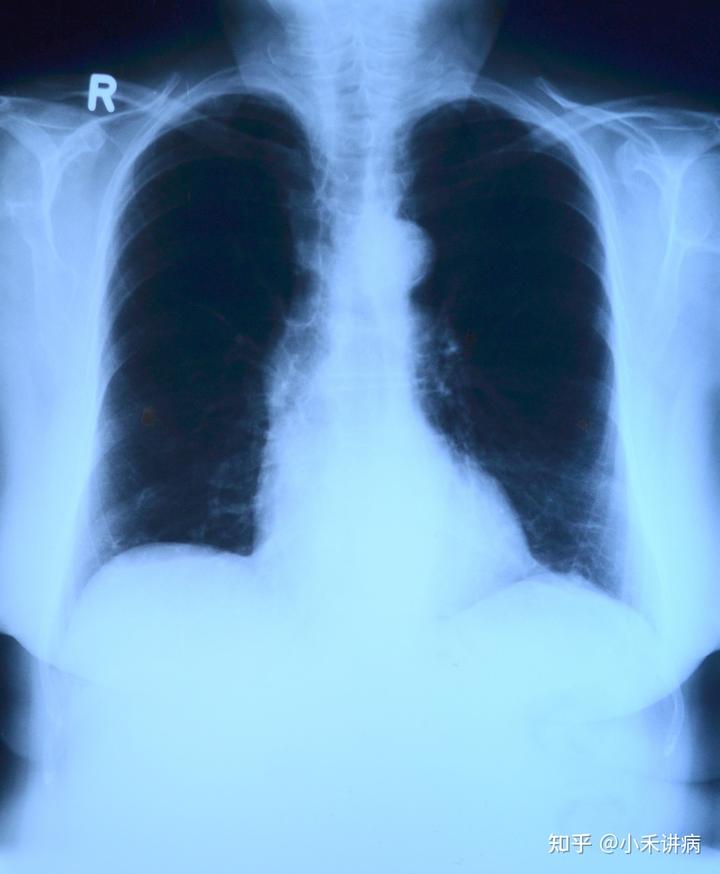

在疫情还尚存在很大不确定性因素的今天,我们更应该珍惜我们的身体。如果身体有异常现象,一定要及时去医院治疗。新冠和呼吸道紧密相关。尤其是要预防肺癌的发生,预防肺癌需不需要每年都做一次CT检查呢?今天就让我们来揭晓答案吧!

那么,什么情况下,必须要到医院去做一次CT呢?有以下症状的患者一定要注意及时去医院做CT。身体出现咳嗽、发热、胸闷气短、胸痛等症状的患者一定要预防肺癌的出现。